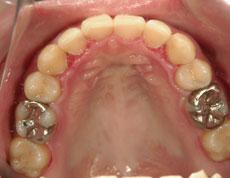

N.N様 裏側矯正

20代 女性 学生

症例: 施術前・施術後

| 装置 | 裏側の装置 |

| 治療方法 | 装置が見える事に抵抗があるとのことで、上下ともに裏側の装置で治療を行いました。 また、上下の前歯の突出感があったため、抜歯をしての治療となりました。 通常は、第一小臼歯を抜歯する事が多いのですが、右下の第二小臼歯が、金属がかぶさっている事、また、上顎の左右の第二小臼歯も虫歯になっている事から上下左右の第二小臼歯を抜歯して治療を行いました。 |

| 治療 | 上下前歯がしっかり引っ込み、口元も綺麗に整いました。咬み合わせも良好な状態です。 この患者様のように虫歯や金属がかぶさっていたり、既にダメージが加わっている歯がある場合はそういった歯を抜いて治療を行う場合もあります。 その場合、通常抜く歯を抜いて治療する場合と、そういったダメージのある歯を抜いた場合とのメリット・デメリットをお話致しますので、その上でどちらの歯を抜くか選んで頂く事が可能です。 |